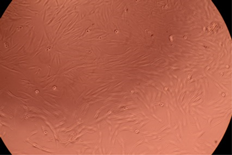

| Sample | Micrographs | ||

|---|---|---|---|

| 24 h | 48 h | ||

| Control |  |  | |

| F127 | 10 µg/mL |  |  |

| 50 µg/mL |  |  | |

| 100 µg/mL |  |  | |

| 200 µg/mL |  |  | |

| F127/PA = 10/1 (g/g) | 10 µg/mL |  |  |

| 50 µg/mL |  |  | |

| 100 µg/mL |  |  | |

| 200 µg/mL |  |  | |